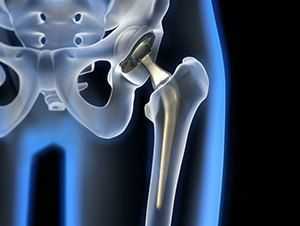

Эндопротезирование тазобедренного сустава